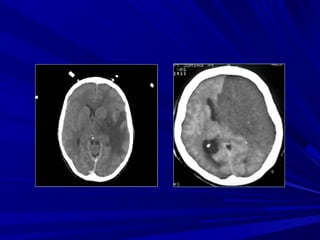

Nhồi máu não cũ

Xuất huyết sau

nhồi máu

Nhồi máu vùng nuôi ĐM não giữaNhồi máu vùng nuôi ĐM não giữa

Nhồi máu vùng nuôi động mạch nãoNhồi máu vùng nuôi động mạch não